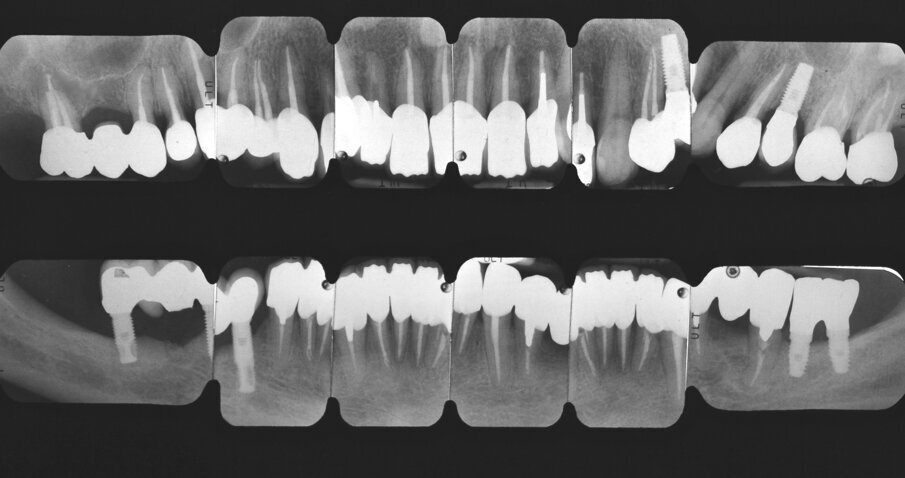

Riguardo al comparto intraorale, dalle radiografie diagnostiche e dall’esame parodontale e occlusale sono emersi aspetti che meritavano una correzione anche nei settori posteriori, ma la paziente ha deciso di effettuare inizialmente il trattamento dei soli gruppi frontali superiore e inferiore demandando a un momento successivo le problematiche dei quadranti posteriori (Figg. 2-6). Nel gruppo frontale superiore si possono notare recessioni gengivali sugli incisivi centrali, che sono anche molto ruotati, e sul canino di sinistra; corone in metallo-ceramica sugli incisivi laterali con esposizione del bordino metallico e una corona in ceramica metal-free sul canino di destra. Inoltre è molto evidente lo squilibrio delle parabole gengivali tra i due canini, per cui per ristabilire un’estetica ottimale sarà necessario anche interessare i tessuti molli eseguendo una chirurgia resettiva sul canino di destra e, al contrario, un lembo a posizionamento coronale sul canino di sinistra (Fig. 7).